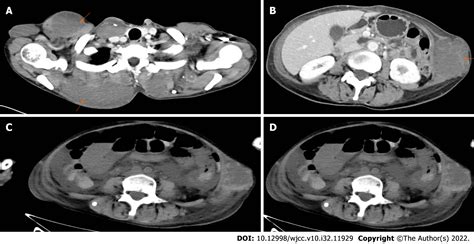

The primary symptom of a Blue Bleb Nevus is its distinctive appearance. These nevi are usually flat or slightly raised and have a blue or bluish-gray color. The blebs or blisters can be small or large and may rupture, leading to temporary changes in the appearance of the nevus. The nevi can occur anywhere on the body but are most commonly found on the trunk and extremities.

The diagnosis of a Blue Bleb Nevus is typically made through a clinical examination. A dermatologist will visually inspect the nevus and may use a dermatoscope to examine it more closely. A dermatoscope is a handheld device that magnifies the skin and allows the doctor to see the structure of the nevus in detail.

In some cases, a biopsy may be performed to confirm the diagnosis. A biopsy involves removing a small sample of the nevus for microscopic examination. This procedure is usually done under local anesthesia and is generally safe and well-tolerated.